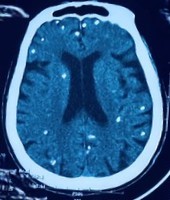

Người bệnh được chuyển lên từ tuyến trước vì rối loạn ý thức đe dọa suy hô hấp, hình ảnh cắt lớp vi tính sọ não và X-quang ngực cho thấy rất nhiều nốt cản quang trong nhu mô não và dưới da vùng ngực-bụng.

Nhiều nốt cản quang trong nhu mô não của người bệnh. Ảnh: Bệnh viện TWQĐ 108

Mặc dù xét nghiệm kháng thể IgM với sán dây lợn âm tính, các tổn thương trên X-quang gợi ý người bệnh trước đây bị nhiễm ấu trùng sán dây lợn, sau đó các nang sán trở nên vôi hóa và tồn tại lâu dài trong tổ chức. Người bệnh được điều trị theo phác đồ bệnh chính, đáp ứng và ra viện tiếp tục điều trị theo tuyến.

Nang sán dây lợn có thể tự thoái hóa hoặc bị vôi hóa, tạo nên nhiều hình ảnh cản quang phát hiện được trên phim X-quang như trường hợp bệnh nhân trên.